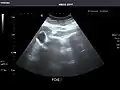

Gallbladder: No stones, wall thickening, or pericholecystic fluid.

Common Bile Duct: Nondilated measuring 1.3 mm at the level of the porta hepatis.